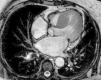

Aos 18 meses de seguimento a doente apresentou agravamento da capacidade funcional por dispneia para esforços moderados (NYHA II). Foi repetido EcoTT: VE com hipertrofia acentuada do SIV basal e boa função sistólica global; VAo aparentemente tricúspide, calcificada, com abertura reduzida, sem possibilidade de realizar planimetria; válvula mitral calcificada com movimento sistólico anterior (SAM). O estudo Doppler revelou aceleração do fluxo com início no TSVE (Figura 3), com pico de velocidade mesossistólico, gradiente VE/Ao máximo 49mmHg e médio 32mmHg, favorecendo a hipótese de obstrução fixa (Figura 3). Não foi visualizado pico de velocidade sistólico tardio, com e sem manobra de Valsalva.

Dadas as limitações do EcoTT, a doente realizou ecocardiograma transesofágico (EcoTE). Este revelou VAo dismórfica, com calcificação acentuada e fusão da cúspide não coronária e coronária esquerda, com área estimada por planimetria de 0,6cm2 (0,27cm2/m2, Figura 4). O estudo com Doppler cor permitiu a diferenciação clara de um fluxo laminar a nível do TSVE e de um fluxo turbulento a nível da VAo, durante toda a sístole, confirmando a suspeita de obstrução apenas a nível valvular (Figura 4).